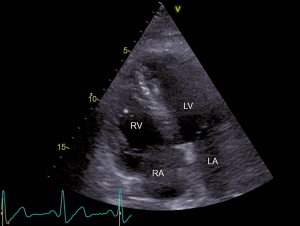

Abb. 3: RV-modifizierter apikaler Vierkammerblick Im rechten Atrium zeigt sich ein grosser, zweischenkliger Thrombus (*), welcher am interatrialen Septum adhärent zu sein scheint (Pfeil). RV = rechter Ventrikel und RA = rechtes Atrium.